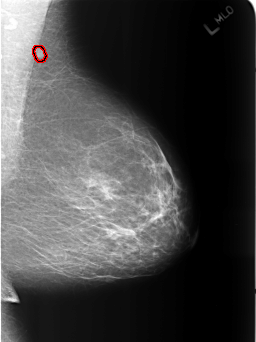

LEFT_MLO LINES 5464 PIXELS_PER_LINE 4096 BITS_PER_PIXEL 12 RESOLUTION 50 OVERLAY

FILE: B_3186_1.LEFT_MLO.OVERLAY

TOTAL_ABNORMALITIES 1

ABNORMALITY 1

LESION_TYPE MASS SHAPE OVAL MARGINS CIRCUMSCRIBED

ASSESSMENT 2

SUBTLETY 4

PATHOLOGY BENIGN

TOTAL_OUTLINES 1

BOUNDARY